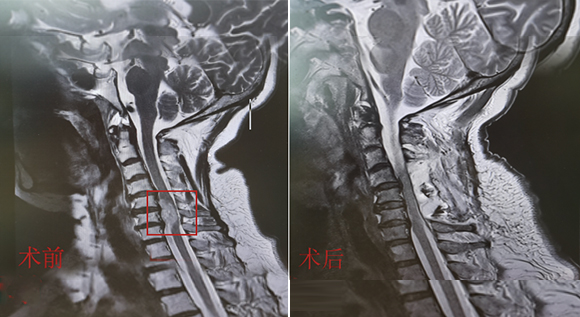

• 寰枢椎脱位椎间融合内固定术 4